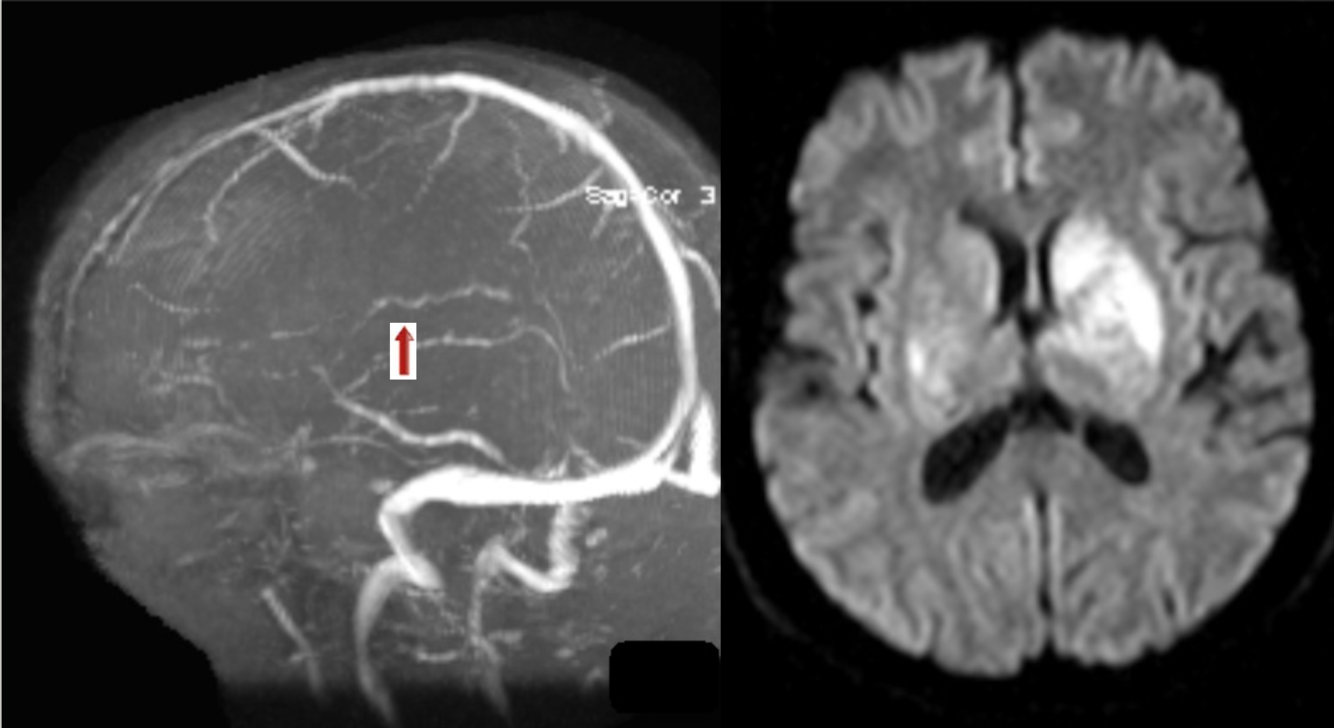

35 y/o F with acute R-sided weakness.

Thrombosis of inferior sagittal sinus